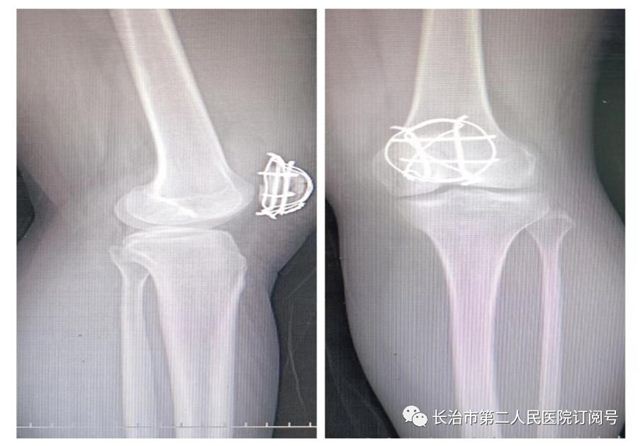

手术治疗

术前